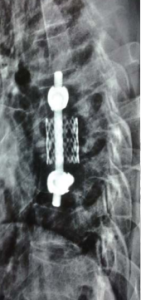

T7 corpectomy was done through a left sided thoracotomy. The resected vertebra was reconstructed using rib graft, a cage and a screw rods construct. Physical Findings